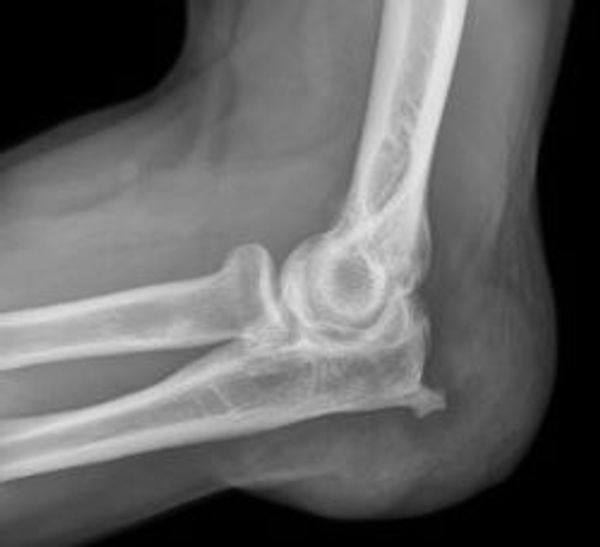

Leestijd: 4 minutenEen bursitis oftewel een slijmbeursontsteking is een – en de naam zegt het al – ontsteking van een of meer slijmbeurzen (bursa) in het lichaam. Het woord bursa komt uit het middeleeuwse Latijn en betekent zakje of portemonnee. Het is een met vocht gevuld ‘stootkussentje’ of schokdemper dat ligt tussen een pees en het bolle gedeelte van een gewricht. Het heeft als taak ervoor te zorgen dat een gewricht zonder wrijving kan bewegen. Slijmbeurzen vinden we onder andere in de schouder, de knie, de elleboog, heup en de hiel. Op alle plekken in het lichaam waar zich bewegende (draaibare) botten (gewrichten) bevinden.

Bij een slijmbeursontsteking maakt de slijmbeurs meer vocht aan, waardoor het zakje uit gaat zetten. Het gevolg is minder ruimte voor het gewricht, dat hierdoor pijnlijk gaat aanvoelen en stijf wordt. Op deze manier wordt bewegen bemoeilijkt. In de meeste gevallen wordt een slijmbeursontsteking veroorzaakt door een overbelasting, vaak door eenzijdige bewegingen, een ongeluk of door een bacteriële ontsteking. De symptomen zijn roodheid, een warm aanvoelend gewricht, pijn en bewegingsbeperking. Vaak nemen de klachten ’s nachts in rust toe. Soms treden ook misselijkheid, rillingen en koorts op.